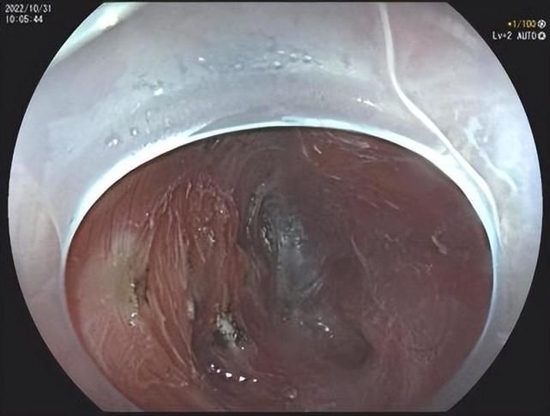

完整剥离

经过术前充分的准备,消化内科陈镇医生为患者实施经内镜粘膜下隧道肿瘤切除术(STER),历时1个小时,直径约3cm的病变顺利切除。术后王大娘无任何不适,经适当禁食及药物治疗后已恢复饮食,术后病理证实为食管平滑肌瘤。

STER手术在食管、胃食管结合部、胃窦等部位,先在黏膜表面开一个小口,随后将内镜深入其中,在黏膜下层建立一个隧道探查并分离病变,在直视下将肿瘤完整切除,同时保留了消化道表面黏膜的完整性,在肿瘤完整切除后,将黏膜隧道的开口使用金属夹进行夹闭,避免了消化道的穿孔,减少了感染等并发症。

该手术具有手术时间短、创伤小、痛苦小、费用低、患者恢复快的优点,可以一次性完整剥离肿瘤,同时保持消化道的完整性,且具有与外科手术相同的治疗效果,术后完全无体表瘢痕。